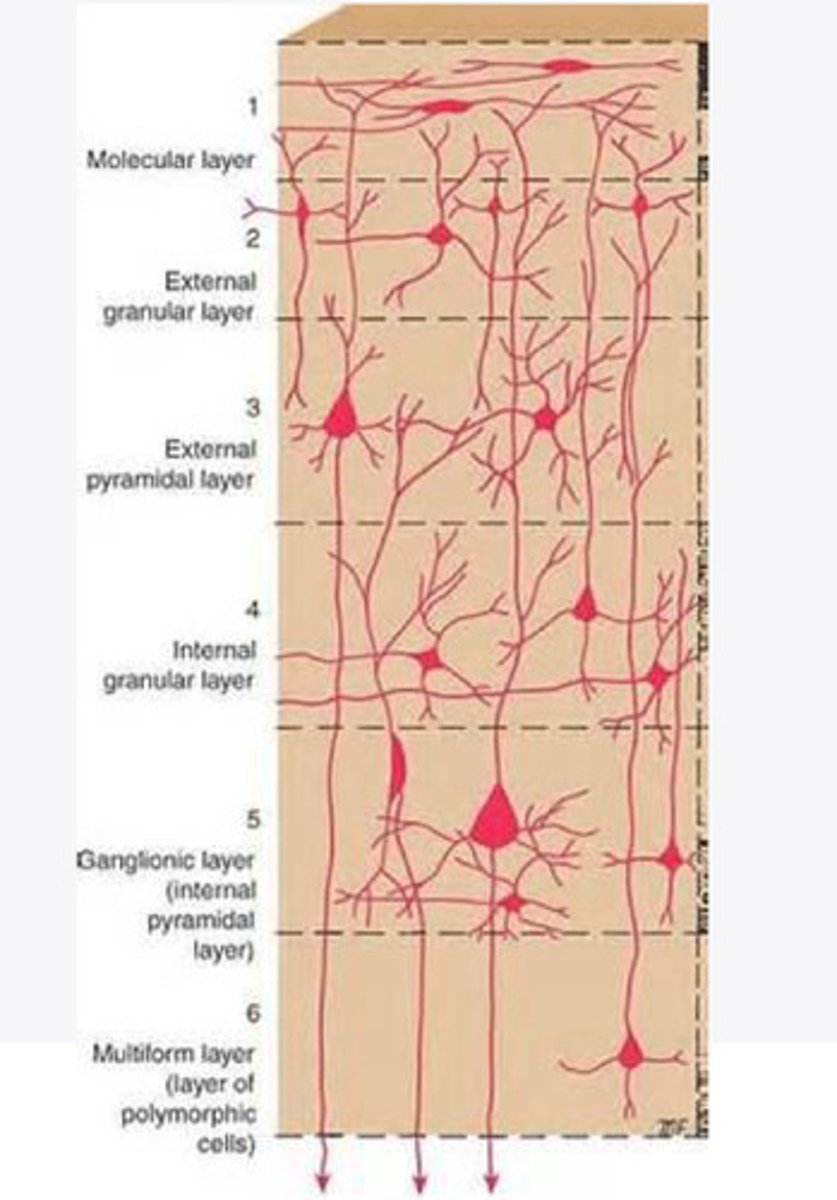

divided into 6 distinct layers, due to varying densities of cell body types within each layer

The cortex of the brain is divided into how many layers? Why is it divided into layers?

Layers of the cortex of the brain pic

2 and 4

What are the layers of the cortex that are associated with input?

3 and 5

What are the layers of the cortex that are associated with output?

molecular layer

What is the name of Layer 1 of the cortex of the brain?

very few cells

Does Layer 1 of the cortex have a lot or few cells?

receives dendrites from internal layers so it may actually function as a coordinating center where layers can communicate action

What does Layer 1 of the cortex do?

1

Every layer sends densities to Layer ____?

1

What layer serves as the "water cooler" of the brain?

external granular layer

What is the name for layer 2 of the cortex of the brain?

receives input from other cortical regions

What is the function of Layer 2 of the Cortex of the brain?

Stellate

What type of cells (stellate/pyramidal) would be most concentrated in Layer 2?

external pyramidal layer

What is the name for layer 3 of the cortex of the brain?

sends output to the other cortical layers

What is the function of Layer 3 of the cortex of the brain?

pyramidal

What type of cells (stellate/pyramidal) would be most concentrated in Layer 3 of the brain?

Layers 2 and 3

What layers are associated with association and commissural fibers?

Layer 3 - axons of cell bodies

Layer 2 - synapse into target areas in Layer 2

What part of the axons is in Layer 2/ in layer 3?

Layer 3 - external pyramidal layer

All axonal cel bodies for association and commissural fibers lie within what layer of the Cortex of the brain?

internal granular

** or called the striate cortex because it is so thick that you can see a line through this layer even in unstrained brain slides

What is the name for the 4th layer of the cortex of the brain?

receives input from the thalamus, geniculocortical layer, and other brainstem areas

What is the function for the 4th layer of the Cortex of the brain?

very thick within the vision, auditory, and somatosensory areas

Is Layer 4 thick or thin within SENSORY areas of the cortex?

Internal pyramidal

What is the name for Layer 5 of the cortex of the brain?

sends axons to the brainstem (corticobulbar) and spinal cord (corticospinal)

What is the function of Layer 5 of the cortex of the brain?

in motor areas of the cortex?

Where is layer 5 very thick in the brain?

the frontal lobe -- very motor heavy

What lobe of the brain will have a thick layer 5 of the cortex of the brain?

the multiform layer

What is the name of layer 6 of the cortex of the brain?

-sends axons back to the thalamus through corticogeniculate fibers

-modulates what information the thalamus sends to the cortex to control the strength of the signal received and modulate what you pay attention to

What is the function of layer 6 of the cortex of the brain?

no

Is layer 6 a motor layer?